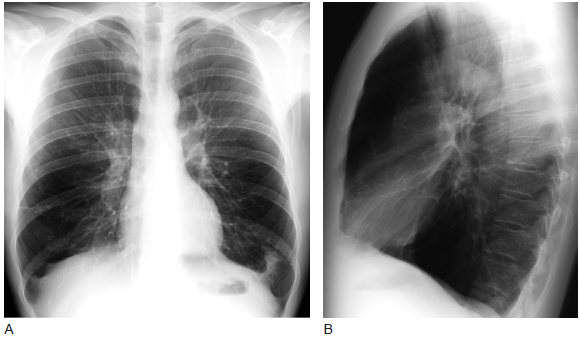

肺气肿的胸片表现

肺气肿的胸片表现,肺气肿胸片典型图片

胸片上小叶中心型肺气肿常表现为上叶显著的肺透光度增高,肺纹理减少